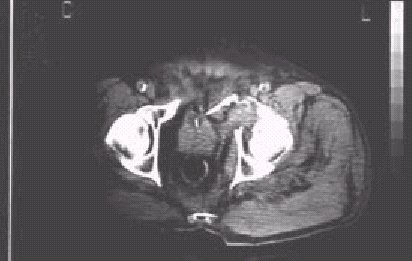

Figura 5.

—Tomografía computerizada de pelvis en la que se aprecia fractura con desplazamiento de cotilo izquierdo.